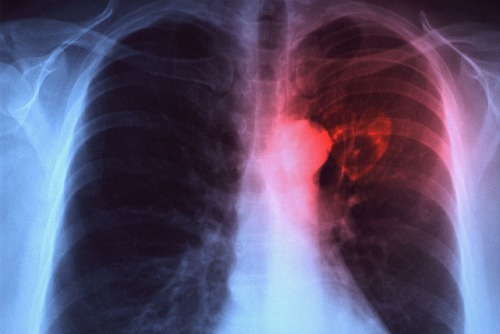

În ultima săptămână, 1681 de persoane din județul nostru au fost diagnosticate cu viroze și pneumonie. Nu mai puțin de 221 bolnavi au fost internați, 203 dintre ei având pneumonie. Pneumonia reprezintă infecţia ţesutului pulmonar, cauzată, în principal, de bacterii, virusuri, fungi şi paraziţi.